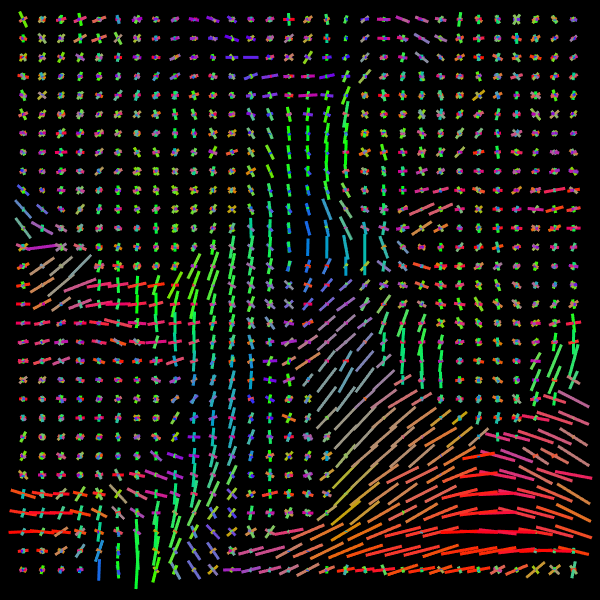

Training stage. We compare the results of the proposed Voxel (VOX) and Neighborhood (NBH) models with two of the SOTA methods which tackle the same task: Diffusion Basis Functions (NNLS) proposed by Ramirez-Manzanares et al. (2007)) and Constrained Spherical Deconvolution (CSD) proposed by Tournier et al. (2007). There are many options to compare distributions, a common comparisson procedure used in this context is to detect peaks and compute the angular error between the real peaks and the estimated ones. However, to compare modes in not a standard procedure for comparing distributions. Among them two notable options are Kullback-Leibler (KL) Divergence and the Wasserstein Distance (also know as the Earth Mover Distance, EMD). Despite its computational cost, EMD has shown to represents more precisely the distribution distance (Levina and Bickel, 2001; Aranda et al., 2011; Arjovsky et al., 2017). EMD represents the minimum cost of transforming a peak distribution into another, weighting by angle. We create a synthetic dataset with gradient table of the Stanford HARDI dataset (Rokem et al., 2015), the eigenvalues of a Diffusion Tensor model fitted to the corpus callosum region, and the SNR computed in such a data (Descoteaux et al., 2011). The estimated SNR depends on image region: most of the measures laid into [20,24]2024[20,24], so we randomly generate data selecting the SNR into [20,30]2030[20,30]. Figure 5 depicts the error for each analyzed model. The vertical axis corresponds to the angle (θ1subscript𝜃1\theta_{1}) between the first PDD and the second one. Meanwhile, the horizontal axis shows the angle between the third PDD and the plane formed by the first two PDDs. The dynamic range of the error maps shows a better performance of the proposed models. We select some predictions for a visual inspection (qualitatively comparison). For illustration purposes, we choose one between the top–101010 and one of the bottom–101010 according to its EMD values for the studied models: VOX, NBH, NNLS, and CSD. The results are presented in Figure 6. The first two columns correspond to the best predictions: the first column shows the target and the second column shows the prediction. The third and fourth columns follow the same order but for the worst predictions. Arrows illustrate the generated PDDs (ground truth). According to the α𝛼\alpha value: blue, orange, and green were used for the first, second, and third PDD, respectively.

Refer to caption

Figure 5: EMD (error) heat-maps by model predictions.